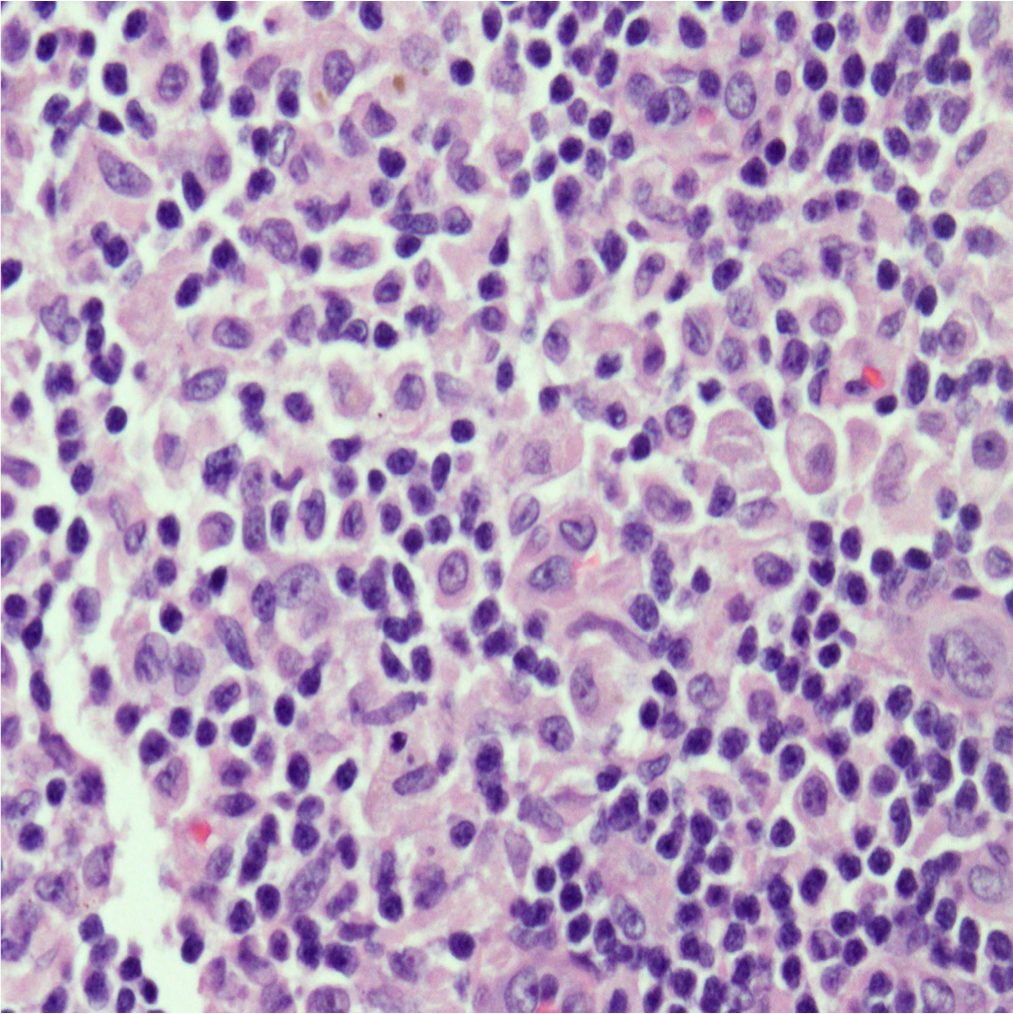

Case Presentation: A 21 year old man presented to his primary care doctor with 4 days of fever and pruritic rash on his hands and feet. Labs showed leukocytosis and transaminitis. He was started on doxycycline for Rocky Mountain Spotted Fever, however tick borne serologies, MonoSpot, HIV, RPR and hepatidities were ultimately negative. He presented to the hospital 4 days later with cough and night sweats. Exam revealed a thin man with cervical and axillary lymphadenopathy, an erythematous rash on his extremities, pedal edema, and petechiae on his bilateral feet. Labs showed worsening transaminitis and eosinophilia. Chest CT showed mediastinal and hilar lymphadenopathy with pneumonitis. Infectious work up for bacterial, fungal, and viral pathogens was negative. Rheumatologic studies were also unremarkable. Flow cytometry showed no B-cell or T-cell abnormalities. He lost 25 pounds during admission and developed thyroiditis and anterior uveitis. Axillary lymph node biopsy revealed cells staining positive for CD1a, S100, CD68, and langerin (CD207) consistent with Langerhans cell histiocytosis (LCH). Treatment with vinblastine and prednisone was initiated with resolution of his symptoms and normalization of his labs.

Diagnosis is tricky as many different organs may be affected and it can resemble more common disorders. It is based on pathologic evaluation of involved tissue and correlation with clinical presentation. No cytogenetic findings are diagnostic, but obtaining a tissue sample (bone, skin, lymph node) in these patients can help shed light on the underlying disease process and lead to earlier diagnosis and treatment.